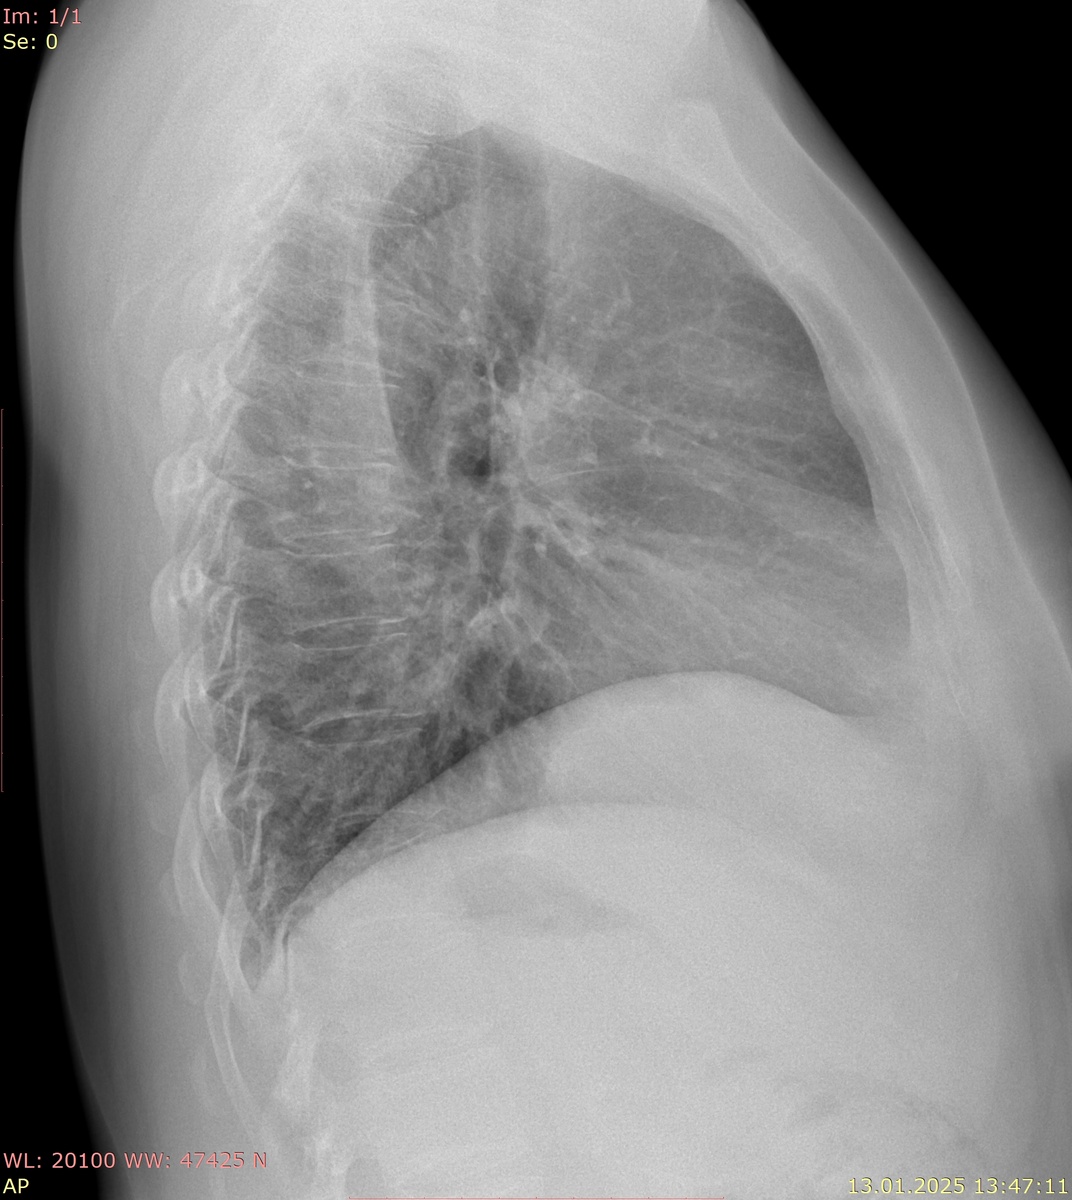

Сосуды легочной артерии.